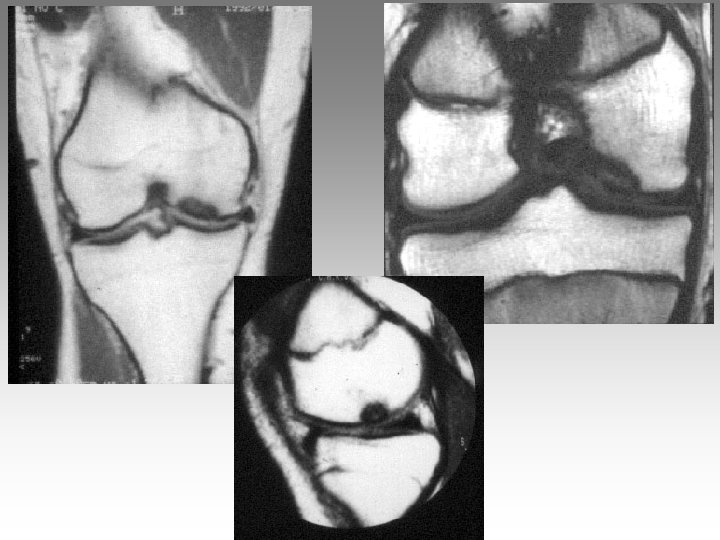

Hanche, T. , fract. fatigue Tendinites bursites, radic. Genou douloureux non traumatique Sémiologie Ponction +++ mécanique inflammatoire Rx inflammation Rx N Rx a. N < 40 ans interligne pincé Arthrose FT - FP contexte +++ > 40 ans Biologie, BS, Rx, IRM, écho interligne normal IRM AND, FF Paget, HOV ONA, OAN OAPH Ostéochond. infection IRM Arthroscopie Scinti. Os. LC Ménisque Coagul. PR, RP, Still, LED, SA…. Goutte, CCA AND ONA Ostéochondrite Pyogène, BK, Gono. , autres Hydarthrose X? Ostéochondromatose Synonite VN, T. , coag.

Genou douloureux non traumatique Sémiologie Ponction +++ mécanique inflammatoire Rx inflammation Rx N Rx a. N < 40 ans interligne pincé Arthrose FT - FP contexte +++ > 40 ans Biologie, BS, Rx, IRM, écho interligne normal IRM AND, FF Paget, HOV ONA, OAN OAPH Ostéochond. infection IRM Arthroscopie Scinti. Os. LC Ménisque Coagul. PR, RP, Still, LED, SA…. Goutte, CCA AND ONA Ostéochondrite Pyogène, BK, Gono. , autres Hydarthrose X? Ostéochondromatose Synonite VN, T. , coag.

Genou douloureux non traumatique Sémiologie Ponction +++ mécanique inflammatoire Rx inflammation Rx N Rx a. N < 40 ans interligne pincé Arthrose FT - FP contexte +++ > 40 ans interligne normal IRM AND, FF Paget, HOV ONA, OAN OAPH infection Biologie, BS, Rx, IRM, écho IRM Arthroscopie Scinti. Os. LC Ménisque Coagul. PR, RP, Still, LED, SA…. Goutte, CCA AND ONA Banal, BK, Gono. , autres Hydarthrose X? Ostéochondromatose Synonite VN, T. osseuse